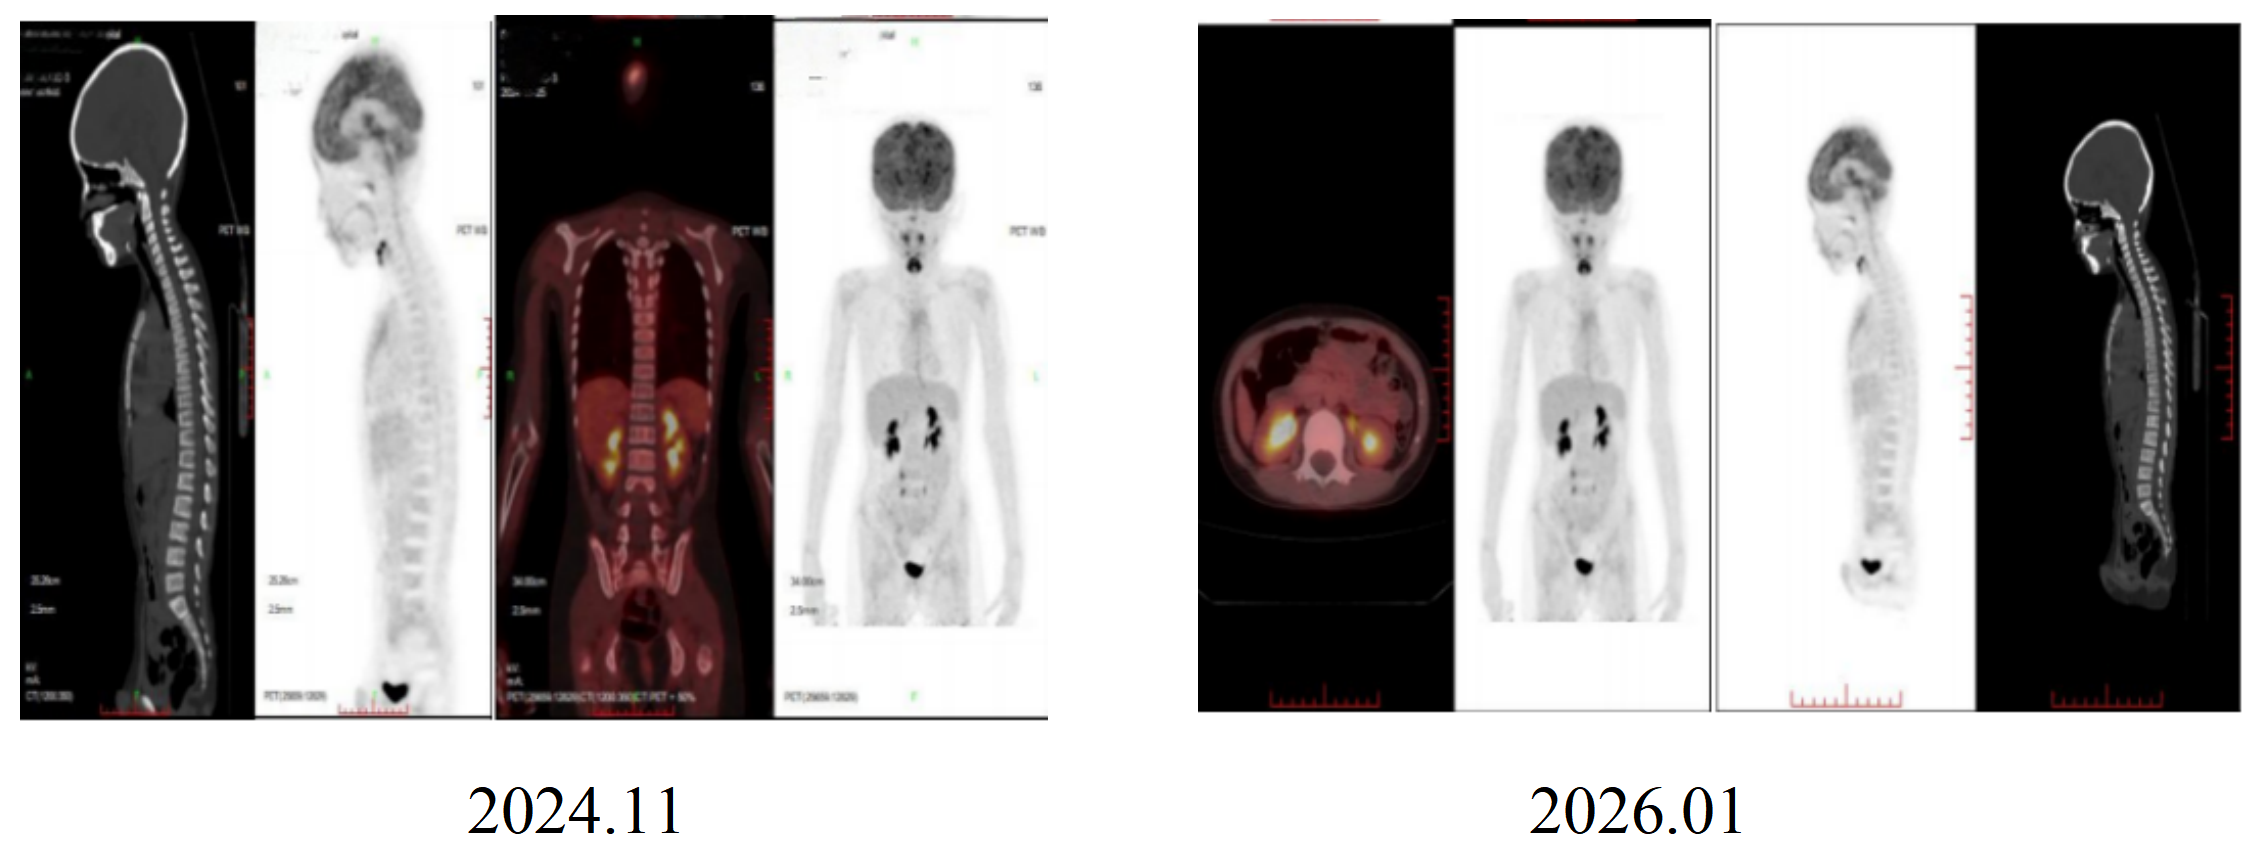

PET-CT(2023.09.15):左肾上腺区术后改变,术区未见肿瘤代谢活性病变,持续CR。

骨髓MRD检测(2023.11):阴性,持续CR。

完成5周期免疫联合化疗后,2023年12月起口服维甲酸(160mg/m²/d,bid,d15-d28)维持治疗。经完整维持治疗后,患儿持续保持CR状态。

PET-CT(2024.11、2026.01):

未见代谢活性增高。

骨髓MRD检测(2024.11、2026.01):

未见肿瘤细胞。